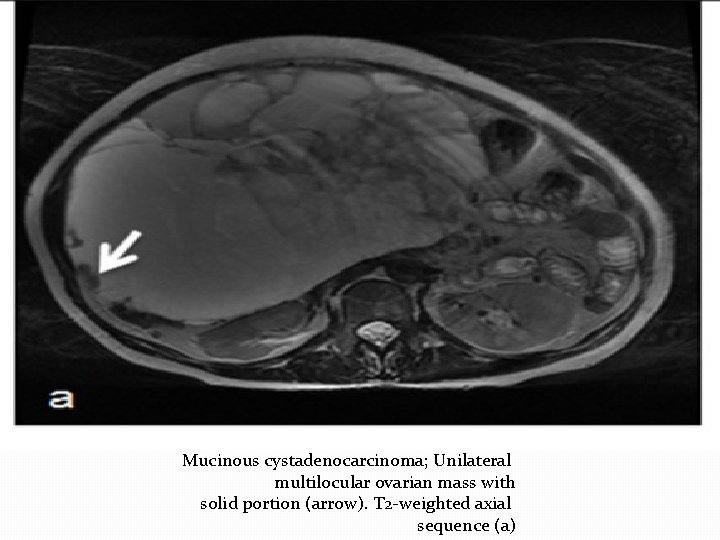

Mucinous cystadenocarcinoma; Unilateral multilocular ovarian mass with solid portion (arrow). T 2 -weighted axial

Mucinous cystadenocarcinoma; Unilateral multilocular ovarian mass with solid portion (arrow). T 2 -weighted axial sequence (a)

T 1 -weighted axial sequence (b),

diffusion-weighted axial sequence b 1000 (c),

T 1 -weighted fat sat axial sequence after gadolinium injection (d).

Macroscopic view (e) of the ovarian mass: multilocular cystic tumor with solid component (arrow

Histological appearance x 10 magnification (f): tumor proliferation with stromal invasion and cytonuclear

Histological appearance x 10 magnification (f): tumor proliferation with stromal invasion and cytonuclear atypia